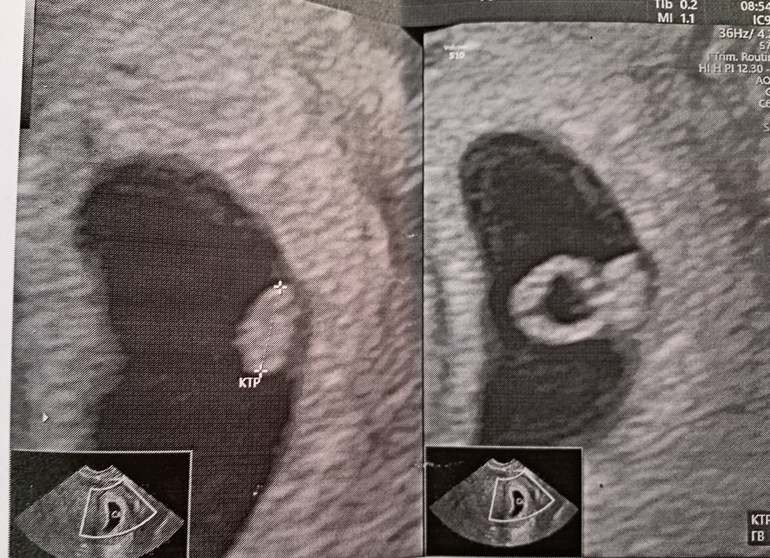

.Ну вообщем.Сегодня по сроку 5,7 нед,так и ставят 6 неделек

ПЯ 34*10*36 свд 26(большевато да?)ото и хгч 32929

КТР 3,8 мой сладенький🌸

СБ+ ритмичное❤️

ЖМ-4мм

желтое тело 21*16